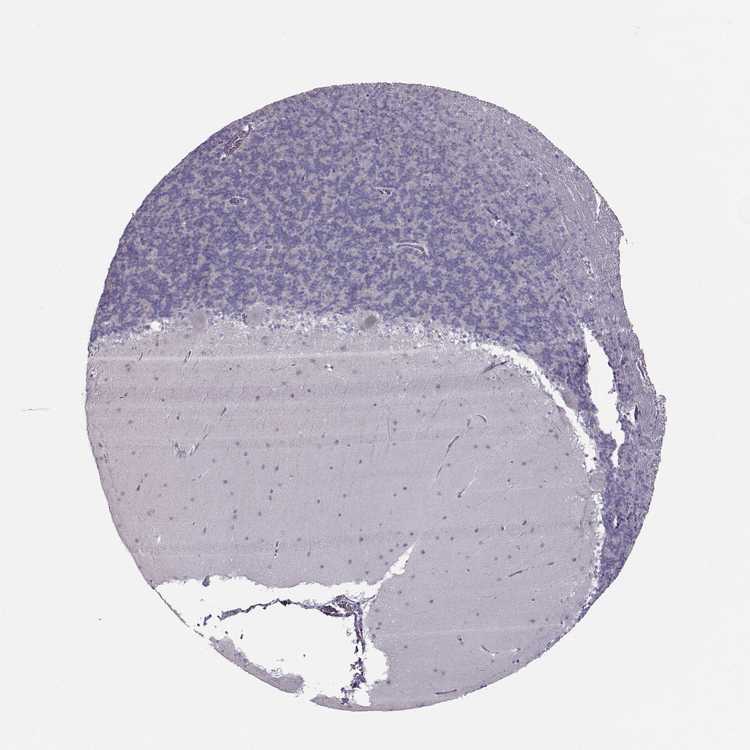

CEREBELLUM - Antibody stainingi

Antibody staining in the annotated cell types in the current human tissue is reported as not detected, low, medium, or high, based on conventional immunohistochemistry profiling in selected tissues. This score is based on the combination of the staining intensity and fraction of stained cells.

Each image is clickable and will lead to virtual microscopy that enables deeper exploration of all samples and also displays staining intensity scores, fraction scores and subcellular localization as well as patient and tissue information for each sample.

Antibody HPA055162

Purkinje cells Not detected

Cells in granular layer Not detected

Cells in molecular layer Not detected